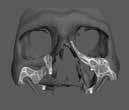

1. a-n. ábrák: Preoperatív CBCT-felvétel a bal alsó 6-os (3.6) fogról. Az axialis (a), coronalis (b) és sagittalis (c) nézeteken a mezialis és distalis gyökerek apicalis harmada körül sugáráteresztő zóna és ép buccalis corticalis csont látható. Egy olyan sablont terveztünk, amely jelezte a csontablak határait az apicalis terület pontos elérése érdekében (d). A mikrosebészeti bevatkozás során a sablont a helyére illesztettük (e), a csontablak határait megjelöltük (f) egy Piezotome CUBE LED kézi-darabba fogott fűrésszel, majd kivágtuk és eltávolítottuk (g és h) az apicalis területhez történő hozzáférés, illetve a mezialis és distalis gyökerek rezekciójának, retrográd preparációjának és retrográd gyökértömésének elvégzése érdekében (i). Végezetül a csontablakot visszaillesztettük és kollagén szivaccsal stabilizáltuk (j). A műtét után közvetlenül készített röntgenfelvétel a 3.6-os fogról (k). A kétéves kontroll során készített CBCT-felvétel: axialis (l), coronalis (m) és sagittalis (n) nézetek.

Egy 63 éves páciens korábban már kezelt bal alsó első nagyőrlőfogából (3.6) eredő mérsékelt fájdalom miatt kereste fel rendelőnket. A kórtörténetében panasza szempontjából releváns információ nem szerepelt. Az elkészült CBCT-felvételen a korábbi kezelések során észre nem vett, jelenleg feltáratlan meziobuccalis csatornát, valamint a mezialis és distalis gyökerek körül kialakult periapicalis elváltozást, és ezt a léziót borító intakt buccalis corticalis csontlemezt láttunk.

Klinikai vizsgálat során vertikális kopogtatási érzékenységet jelzett. A fog körül mérhető szondázási mélység és a fogmobilitás fiziológiás volt. A CBCT-felvételen nem észleltünk a csontos regeneráció megindulására utaló jeleket (1. a–c. ábrák). A korábban gyökérkezelt, gyökértömött és revideált 3.6-os fog esetében az alábbi diagnózis került felállításra: periodontitis periapicalis symptomatica. A panaszokat okozó fog további ellátása során navigált endodonciai mikrosebészetet kívántunk alkalmazni. Az alsó állcsontról intraorális szkent (TRIOS, 3Shape) készítettünk, és a felszíni topográfiát tartalmazó STL fájlt, valamint a CBCT-felvétel készítése során nyert DICOM fájlokat a Blue Sky Bio szoftver segítségével egyesítettük. A sebészi sablon megtervezésére az így kapott háromdimenziós képet használtuk. A sablon kialakítása során arra törekedtünk, hogy a sablon egyértelműen meghatározza a gyökércsúcsi terület eléréséhez szükséges csontablak határait (1. d. ábra)